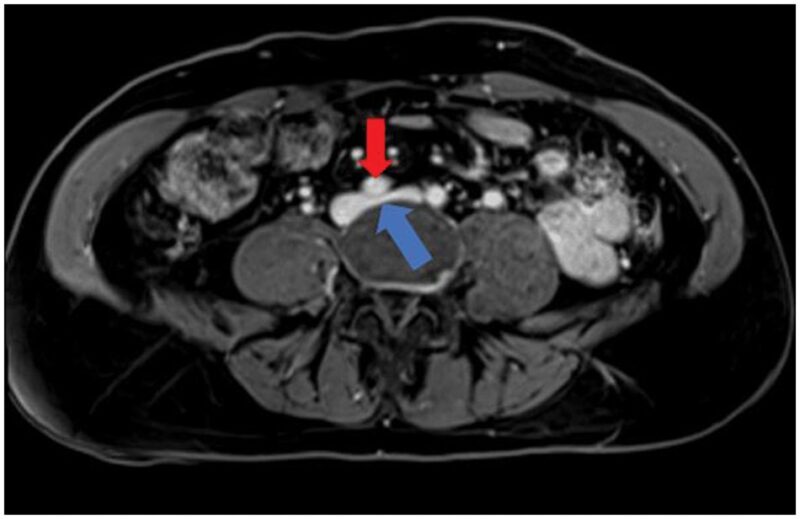

84-year-old man with fever and lower back pain

An 84-year-old man presented with a fever and lower back pain. He had no prior genitourinary, gastrointestinal, respiratory, or systemic symptoms.

Published Date: February 20, 2026

Tags:

CT

,

MRI

Musculoskeletal

Pathology